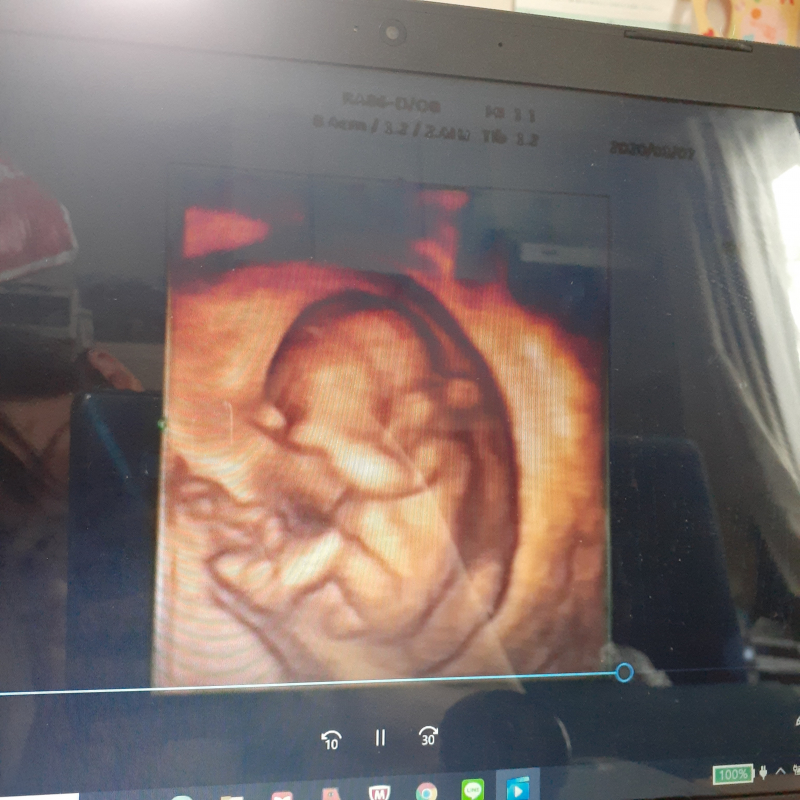

先日12週4日の時に、妊婦健診に行ってきました。

性別が分かると嬉しいのですが、4Dエコー写真から、性別は分かりますでしょうか?

また、まだこの時期では、分からないでしょうか?

せっかくご相談いただきましたが、まだ週数的には性器がはっきりしていない時期で、医師でも診断することは困難です。